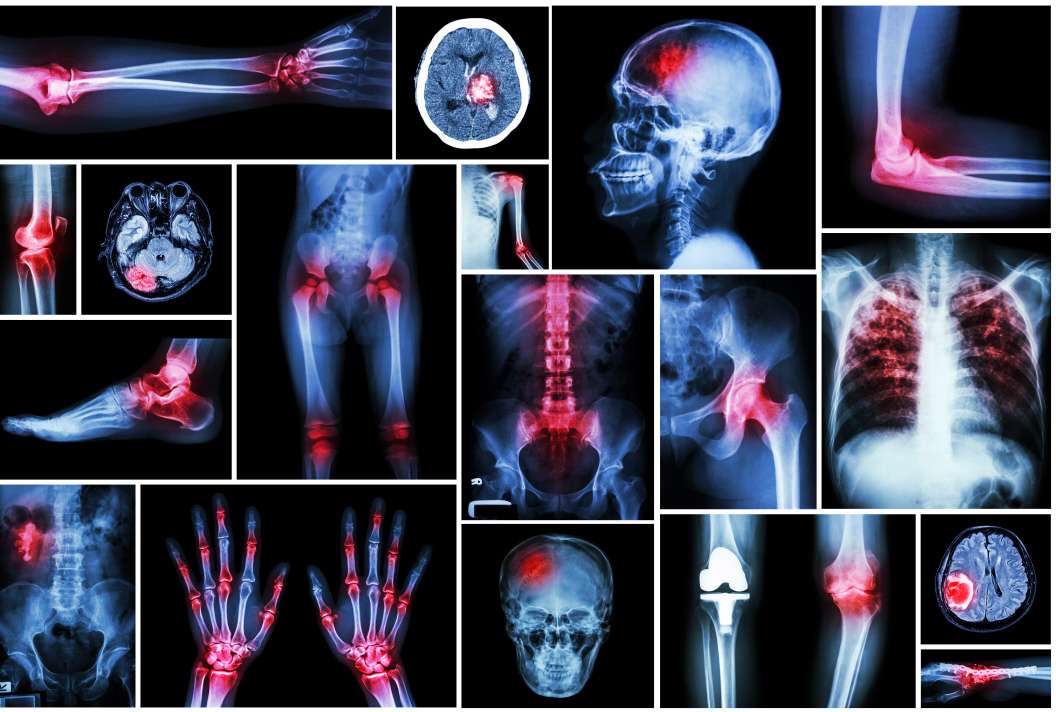

Multiple injury claims can include:

- Multiple orthopaedic injuries or fractures

- Maxillofacial (ENT, vision etc)

- Musculoskeletal injuries

- Psychological injuries

- Nerve and neurological injuries

- Injuries to internal organs